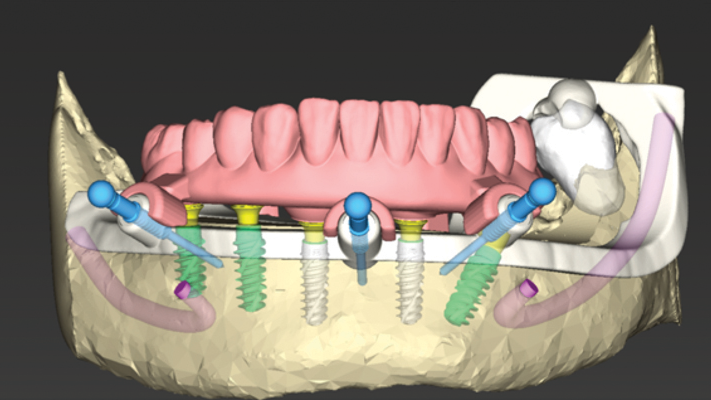

Edentulism in the posterior maxillary region presents a challenging scenario for dental implant rehabilitation due to vertical ridge dimension bone loss and the close proximity to the floor of the maxillary sinus. In addition, alveolar ridge width loss and thinning of mucosa is a common clinical scenario in areas of long term tooth loss. To … Read more